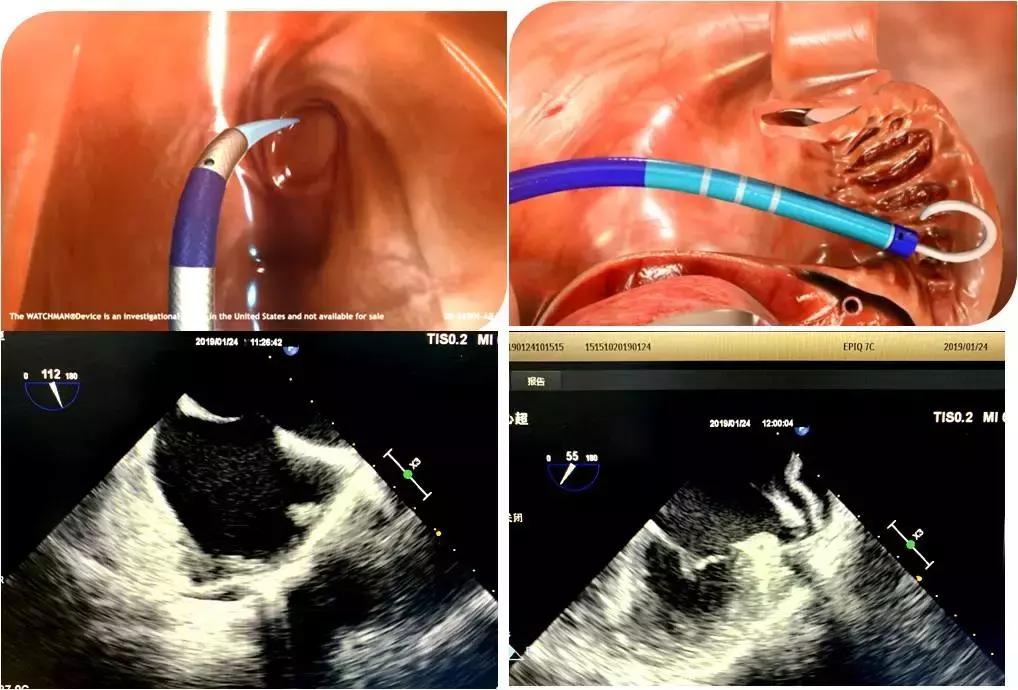

房颤最主要的并发症是血栓栓塞,其中90%以上血栓来源于左心耳。左心耳封堵为心房颤动患者预防脑栓死提供技术支持,逐渐成为有华法林禁忌或不能长期口服华法林患者抗凝治疗的常规选择,很多房颤患者还伴发风湿性心脏病、先天性心脏病及缺血性心肌病、瓣膜病等问题,情况往往综合而复杂。为了准确评估左心耳构造以选择合适的封堵器和植入位置,并对术中穿刺关键步骤及植入准确性实时监测,经食道超声心动图(TEE)越来越多的应用于心脏介入手术的术前及术中评估。

于2019年1月24日上午,心内科主任马峰,心内科副主任潘军强在介入室对一例房颤患者进行左心耳封堵术,超声科郑瑜主任为该患者实施了术中经食管超声心动图监测,清晰显示了房间隔的穿刺,并多平面多角度测量左心耳的超声径线,监测鞘管进入左心耳根部,展开与释放封堵器,并及时评估了封堵器的最终位置、稳定性等,经食道超声的“慧眼“监测为该心脏手术的顺利进行提供了有力保障。